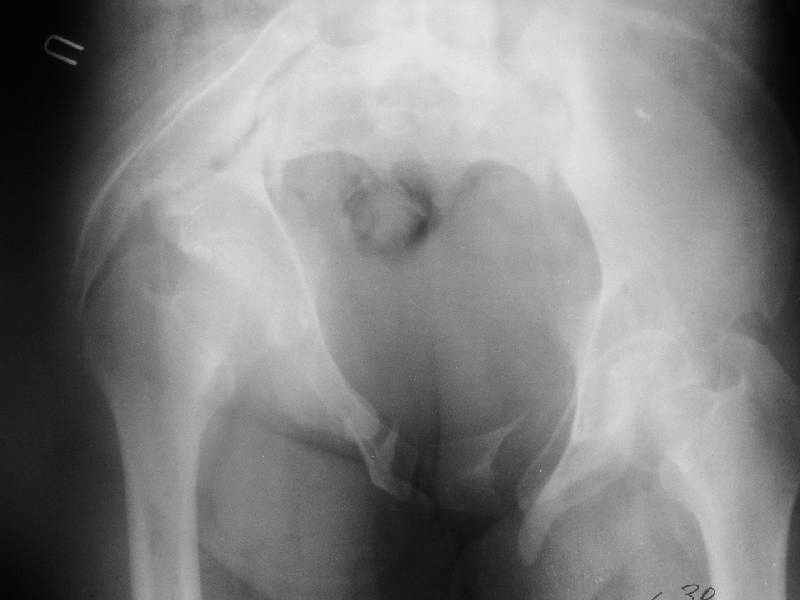

Картина на сегодня:

В настоящее время больная ходит без дополнительной опоры, боль в области таза не беспокоит, неудобств при сидении не испытывает, свободно проходит расстояние в 2-3км. Отмечается незначительная хромота, периодические боли в поясничной области низкой интенсивности, не требующие приема медикаментов, кроме того имеется вагинальный импинджемент. Срок после операции 1 год и 2 месяца.Было бы интересно услышать ваши комментарии. С уважением Агалаков М.В.